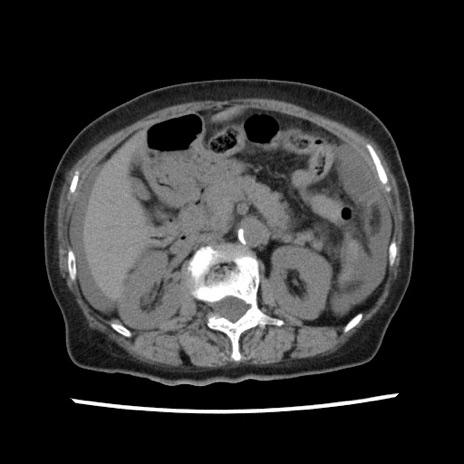

冠状断像

【症例】80歳代女性

【主訴】腹痛

【現病歴】8時間前から腹痛あり来院。

【既往歴】糖尿病、脂質異常症、子宮体癌にて子宮全摘術

【身体所見】意識清明・会話良好だが腹痛で苦悶様、全腹部にわたって反跳痛と圧痛あり

【データ】WBC 13600、CRP 0.14、LDH 224、CK 90